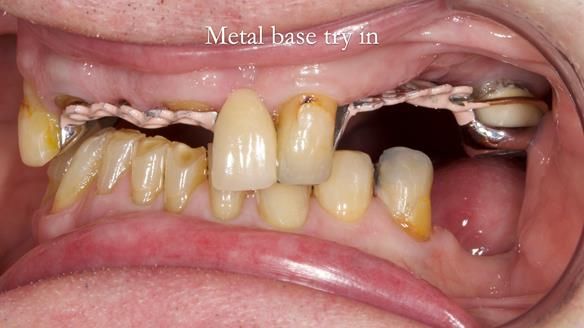

This edition features the case of Edgar, who sought help for a poorly fitting, acrylic-based partial denture that rocked, affected his speech, and caused discomfort. After considering various treatment options, including dental implants, Edgar opted for a metal-based removable partial denture, designed by myself with input from my technician, Rowan Garstang.

Treatment Process: I provided the clinical work while Rowan Garstang delivered the technical aspects. The treatment required fifteen visits to fit and review Edgar.